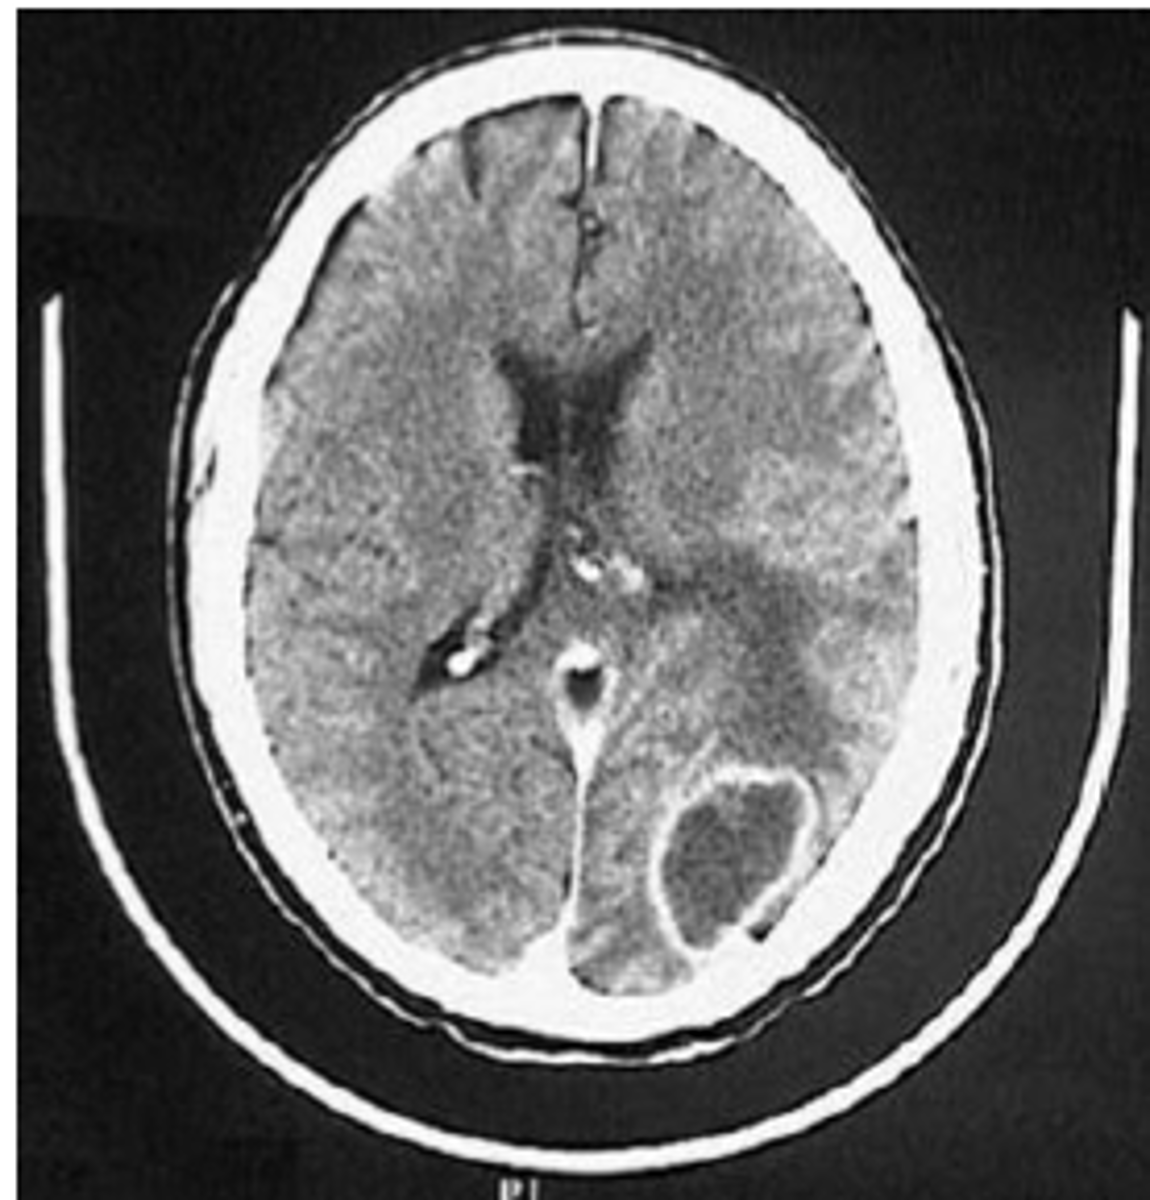

CT scan of ___ shows numerous minute punctate hemorrhages with blurring of grey-white interface.

Diffuse axonal injury

- most significant cause of morbidity in patients with TBI

- traumatic deceleration

Hemorrhages are seen as [hyper/hypo]dense areas on CT scan, while infarcts are [hyper/hypo]dense parenchymal areas on CT scan.

Hemorrhages = Hyperdense

Infarctions = Hypodense